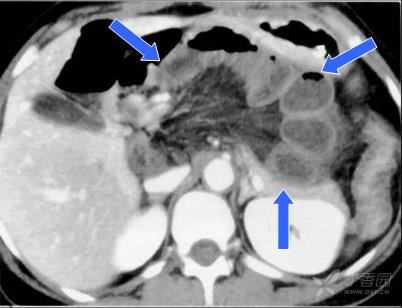

由于从裂孔疝出后并无一限制的疝囊,表现同于一般闭襻型肠梗阻,视裂孔大小,疝入肠管绞窄的严重性可能较之一般疝入陷窝者更甚。由于发生裂孔位置不定,又多在其游离缘,故无恒定的腹部CT定位,所以判断进入疝囊内拥挤、扩张的闭攀肠管及受绞窄增粗、聚集的肠系膜血管非常重要。

急性腹痛,有腹部手术史。 手术诊断: 经肠系膜裂孔疝。